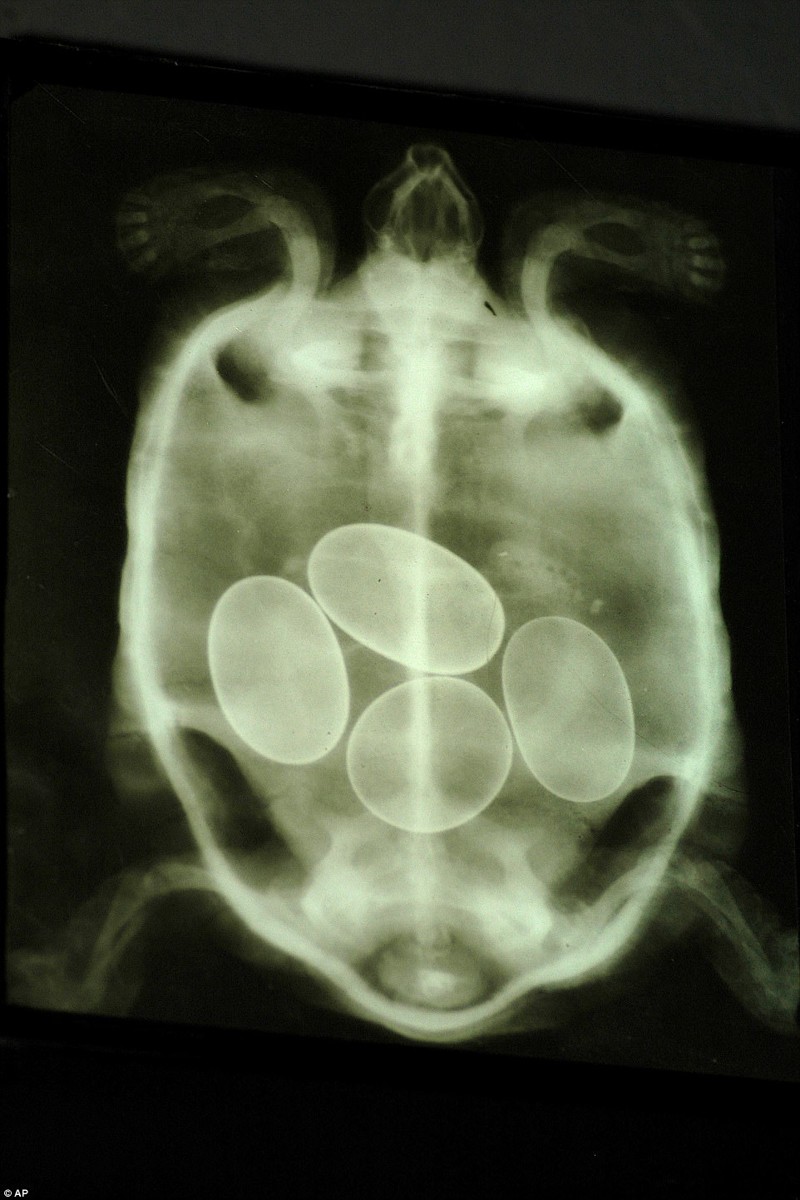

Как выглядит беременность животных на рентген-снимках (12 фото)

Представляем вашему вниманию серию интересных рентгеновских снимков, на которых можно рассмотреть, как располагаются будущие детеныши енота, летучей мыши или, скажем, бородатой ящерицы в животах их мам.

Черепаха